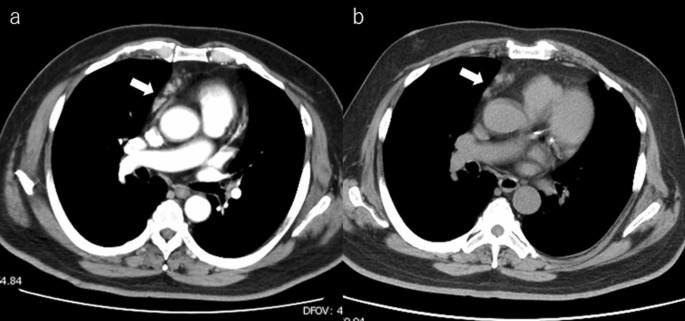

В хирургическое отделение поступил мужчина 66 лет с солитарной опухолью печени. В анамнезе у пациента был РА, по поводу которого он получал МТХ в дозе 14 мг/неделю, эссенциальная гипертензия, бронхиальная астма и дислипидемия. Ранее ему была проведена КТ грудной и брюшной полости в связи с повышенным уровнем С-реактивного белка (СРБ), которая показала увеличение лимфатических узлов средостения и солитарную опухоль печени диаметром 8 см (рис. 1).

Рисунок 1. КТ-снимки средостения, показывающие небольшое увеличение лимфатических узлов при: а) при постановке диагноза; b) спустя месяц после отмены МТХ.

Патоморфологическое исследование удаленного лимфатического узла не выявило отклонений. Размеры лимфатических узлов средостения через 1 месяц после отмены МТХ не изменились (рис. 1б). Послеоперационный период протекал без осложнений, пациент был выписан на 7-е сутки после вмешательства. При контрольном осмотре через 9 месяцев после операции данных, указывающих на рецидив, не было.